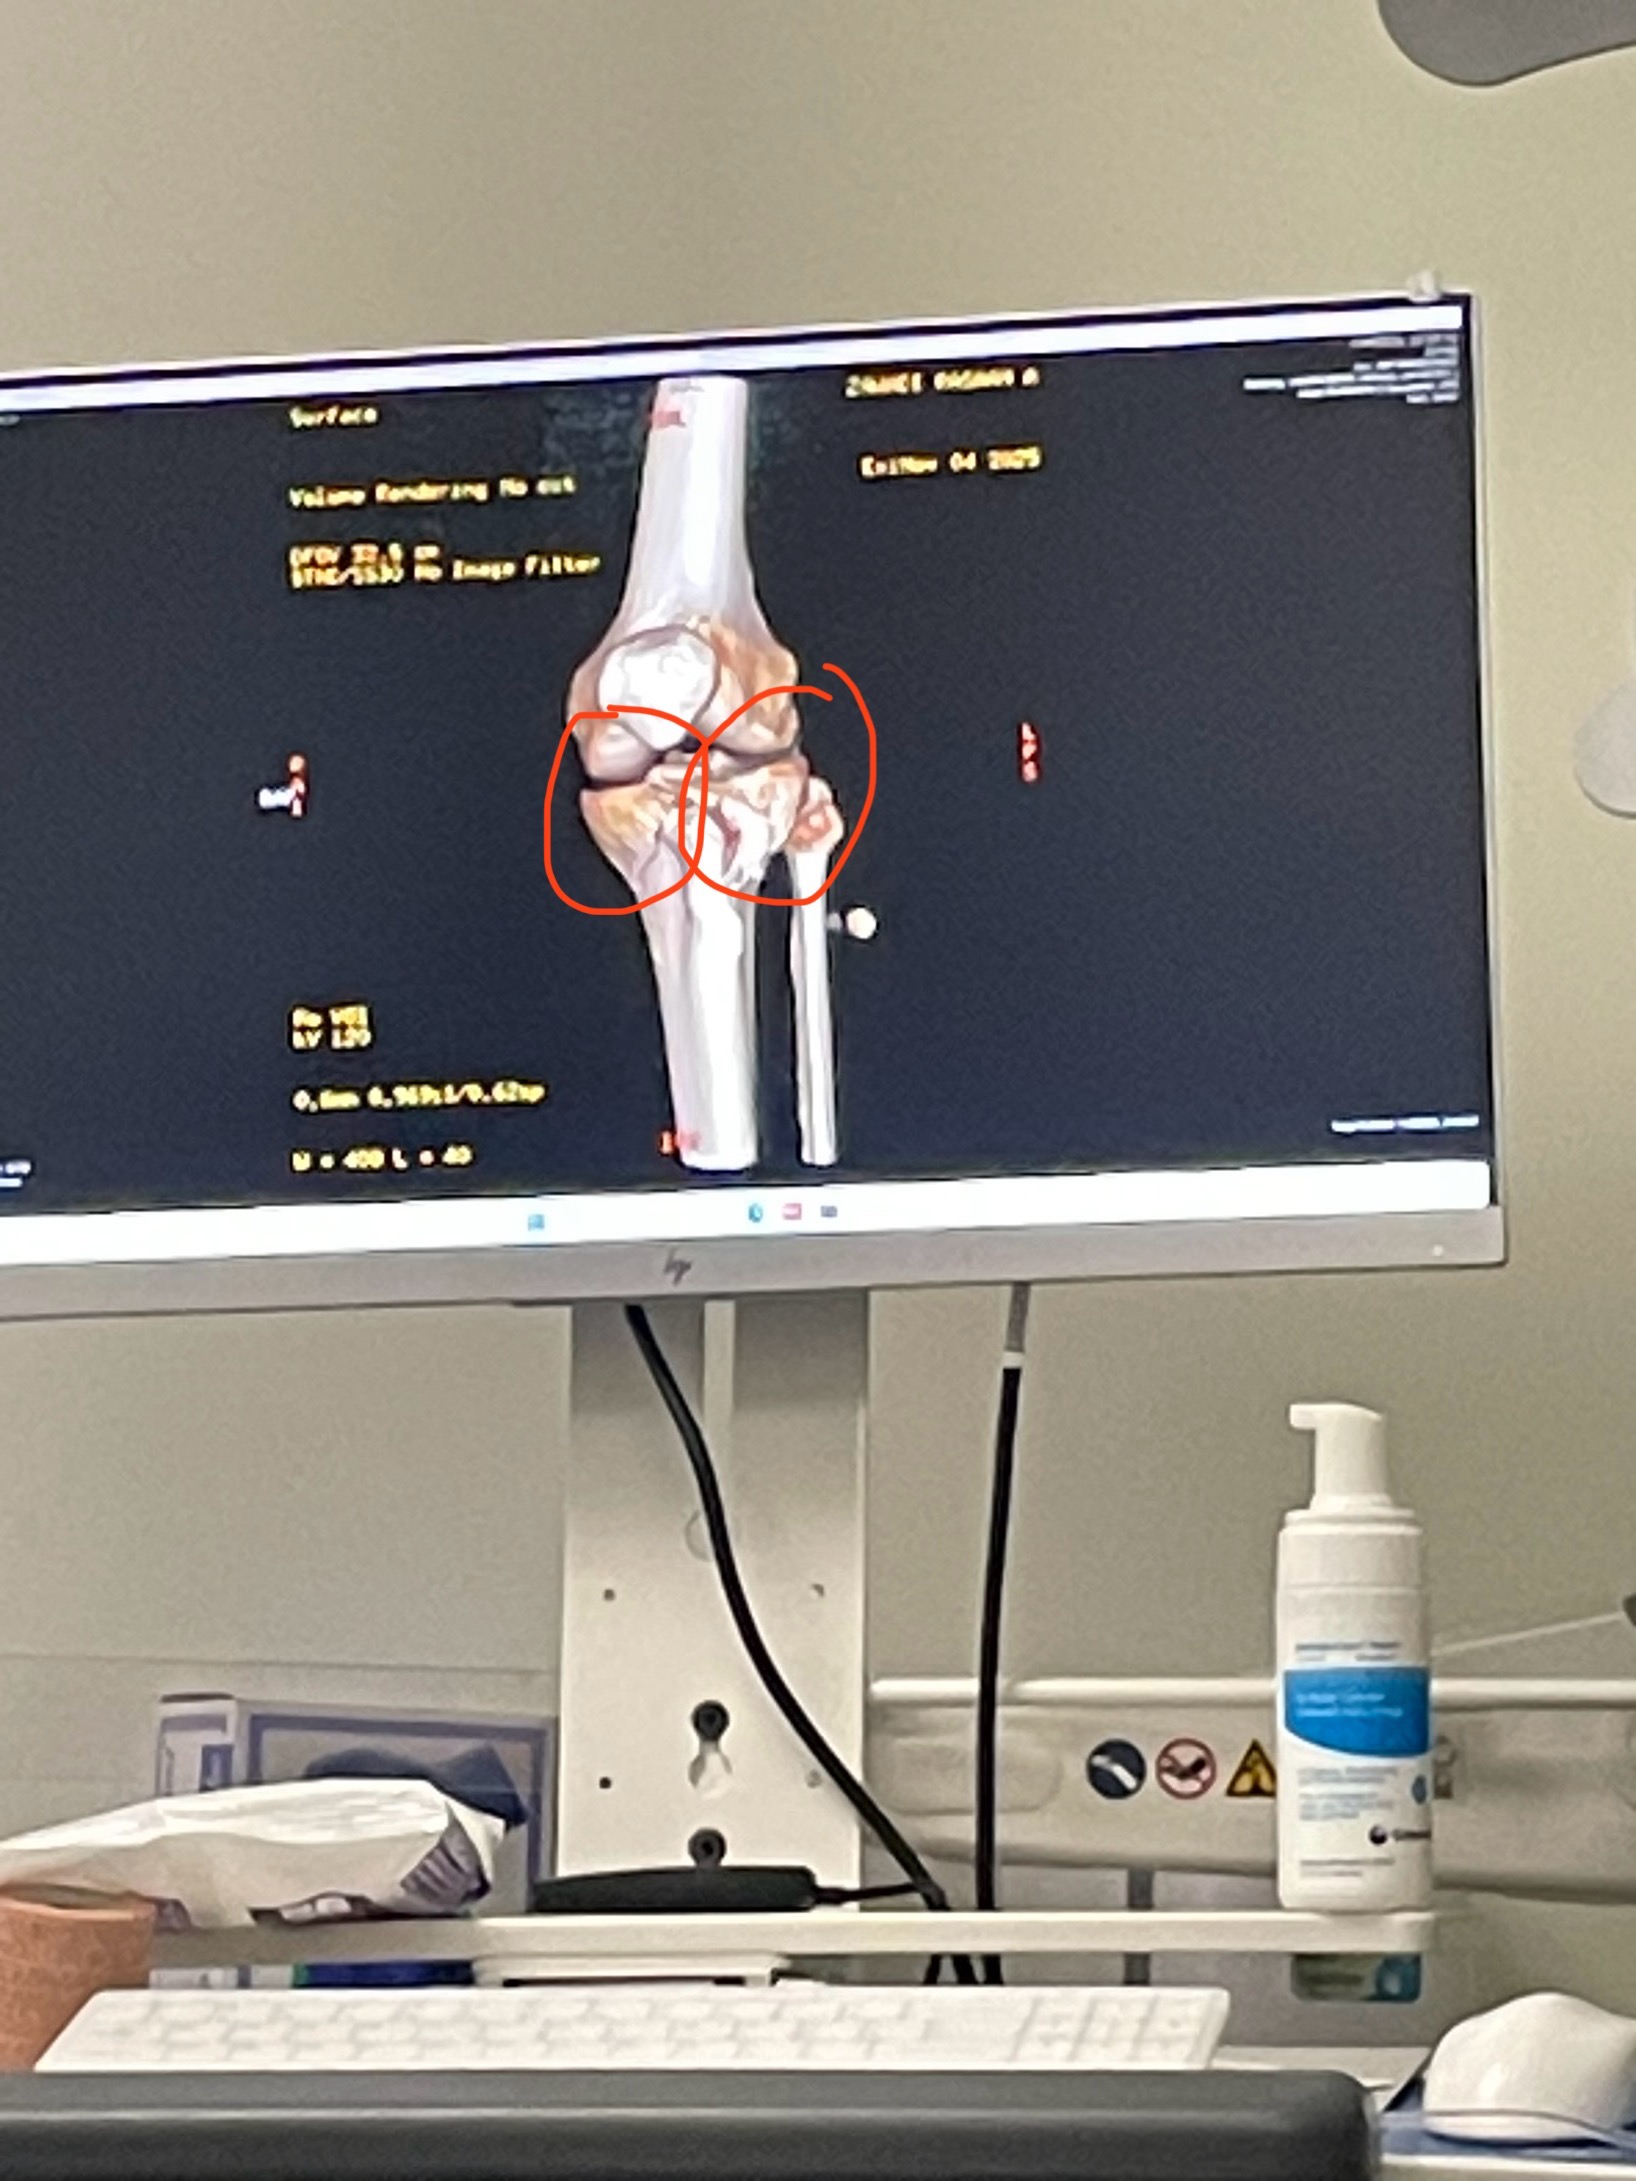

Hi, my name is Ra (Ray). While in the field service and repairing vehicles, I was badly injured. A vehicle that had more damage than I was aware of crushed my legs into a wall. Both legs suffered breaks, but the left one sustained more damage, causing me to be hospitalized for an undetermined amount of time. The surgery went well. I received two plates and screws on each side of my shin bone to seat my thigh bone at the knee. I most likely won’t be walking for some time. With healing and rehab, I could be out of commission for 6 months to a year. I’m not asking for your support the whole time, just enough to get me through the first couple of months. The amount will allow me some time to heal and get other mechanics/technicians to carry on until I can get back to keeping you, my wonderful friends, customers, and family, on the road. This is a tough time we all are facing in this nation, from the last and current administrations' dealings concerning the people’s resources. If you have nothing to give, the effectual prayers of the righteous will avail much. Thank you in advance.